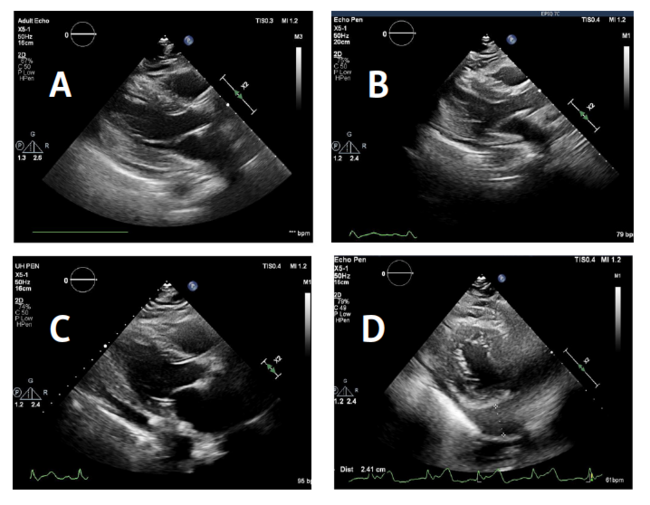

In addition to anchor number, anchor length may also contribute to the development of pericardial effusions. In the Amulet IDE trial, the Amulet occluder device had a higher rate of pericardial effusion compared with the Watchman Legacy (22/903 [2.44%] vs 11/896 [1.23%]).11 This higher rate of pericardial effusion may be related to longer fixation anchors. The Amulet anchors are 2.2 times longer compared with the effective length of the Watchman anchors (Figure 2 and Figure 3). Since total wall (LAA + pulmonary artery) thickness is approximately 1.55 mm, longer anchors could perforate with less manipulation.